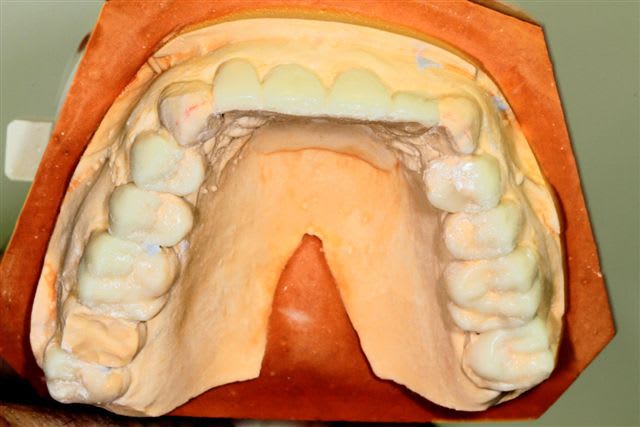

Il semble évident que ceci ne peut être traité que de façon globale, mais la difficulté est de le faire comprendre à la patiente, qui veut seulement un "sourire".

Donc dans un premier temps pano, pour bilan et empreintes pour essayer de lui faire comprendre l'étendue du problème.

premier wax up à minima

Mais autant un wax up ça nous parles, autant la patiente ne déclenche pas, et commence à douter.